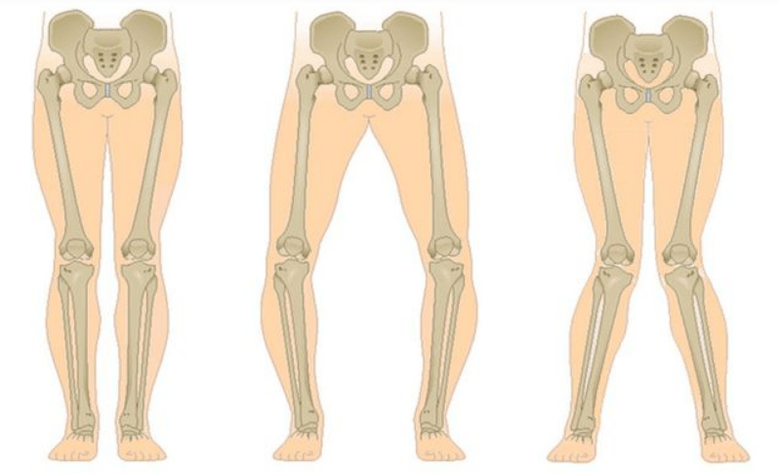

The last stage of gonarthrosis is distinguished by the fact that the pain becomes almost constant, causing anxiety not only when walking, but also at rest, and even at night, when patients have to look for a comfortable position to sleep.Movements are more limited: it is difficult to completely bend and straighten the leg.The joint deforms and increases in volume.A valgus (X-shaped) or varus (O-shaped) deformity of the legs is often observed.Gait becomes unstable and waddles.In severe cases, a cane or crutches are necessary.

With osteoarthritis (osteoarthritis), in addition to the gradual destruction of cartilage, loss of its elasticity and cushioning properties, bones are gradually involved in the process.Under load, sharp edges (exostoses) appear, which are incorrectly considered "salt deposits" - with classic osteoarthritis, no salt deposits occur.As osteoarthritis progresses, it continues to “eat” the cartilage.Then the bone deforms, cysts form on it, all structures of the joint are affected and the leg bends.

Depending on the number of joints affected, we distinguish between unilateral and bilateral knee osteoarthritis.